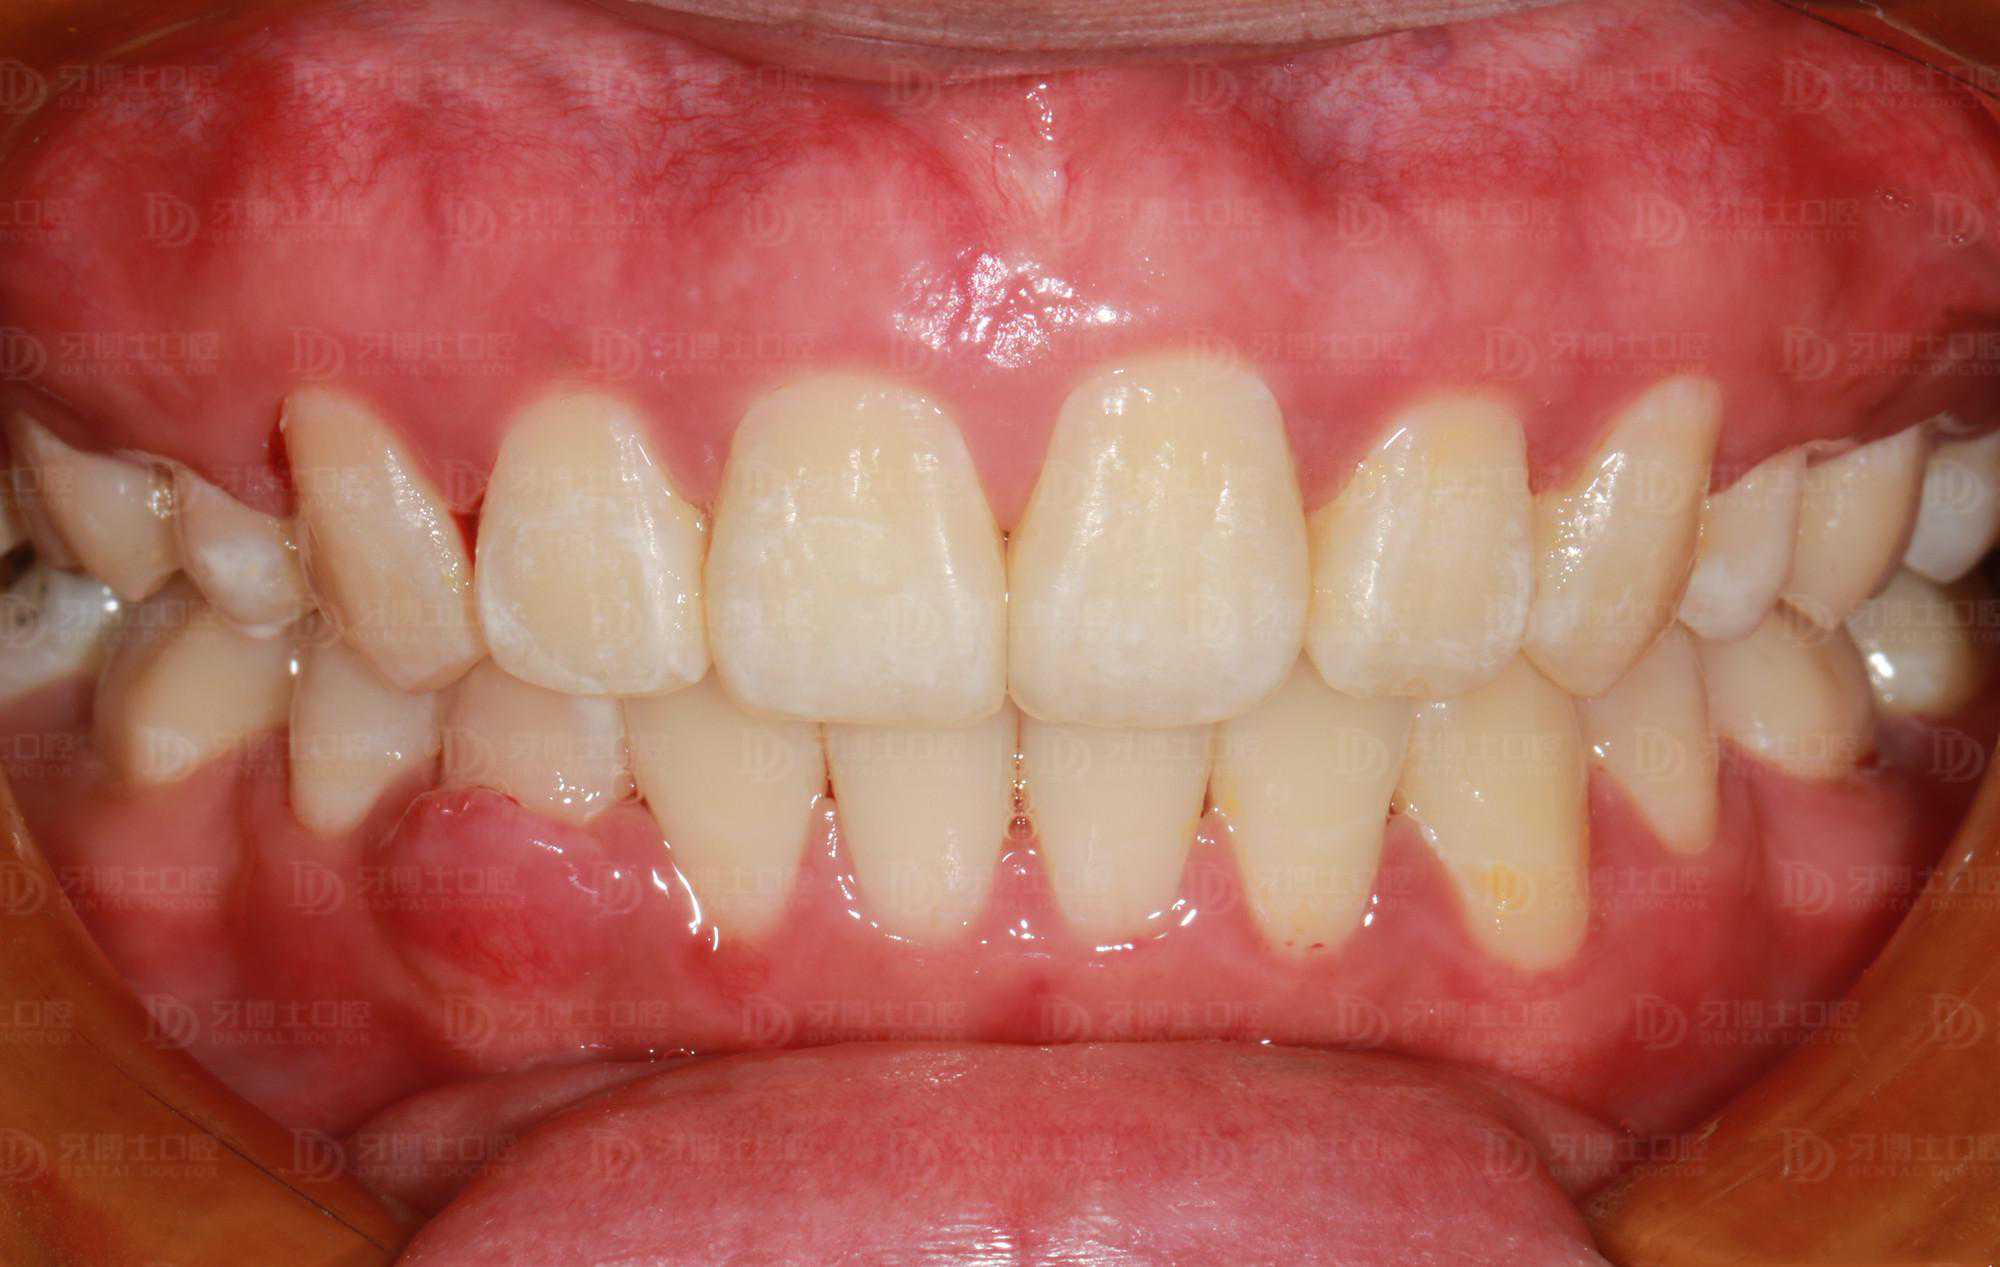

矫正前牙列不齐,并有牙龈炎、牙结石,刷牙时会出血,同时美观度较差,影响容貌。

牙齿排齐内收,更易清洁了,牙周问题明显改善很多,面部整体美观度增加,笑容更加自信。